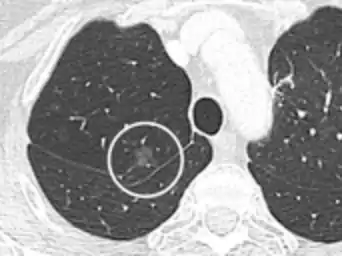

CT image showing ground-glass nodule (circled).

Nodular

There are numerous potential causes of nodular GGOs which can be broadly separated into benign and malignant conditions. Benign conditions potentially leading to the formation of nodular GGOs include aspergillosis, acute eosinophilic pneumonia, focal interstitial fibrosis, granulomatosis with polyangiitis, IgA vasculitis, organizing pneumonia, pulmonary contusion, pulmonary cryptococcus, and thoracic endometriosis. Focal interstitial fibrosis presents a unique challenge when differentiating from malignant nodular GGOs on CT imaging. It is typically persistent over long-term imaging follow-up and shares a similar appearance to malignant nodular GGOs.[9]

Pre-malignant or malignant causes of nodular GGOs include adenocarcinoma, adenocarcinoma in situ, and atypical adenomatous hyperplasia (AAH). One large review study found that 80% of nodular GGOs which were present on repeated CT imaging represented either pre-malignant or malignant growths. Differentiating between pre-malignancy and malignancy on the basis of CT alone can pose a challenge to radiologists; however, there are several features that are indicative of pre-malignant nodules. AAH is a pre-malignant cause of nodular GGO and is more commonly associated with lower attenuation on CT and smaller nodule size (<10 mm) compared to adenocarcinoma.[10] In addition, AAH often lacks the solid features and spiculated appearance that are often associated with malignant growths.[9] In contrast, as adenocarcinoma becomes invasive it will more often cause retraction of adjacent pleura and may show an increase in vascular markings. Nodules >15 mm almost always represent an invasive adenocarcinoma.[9][10]